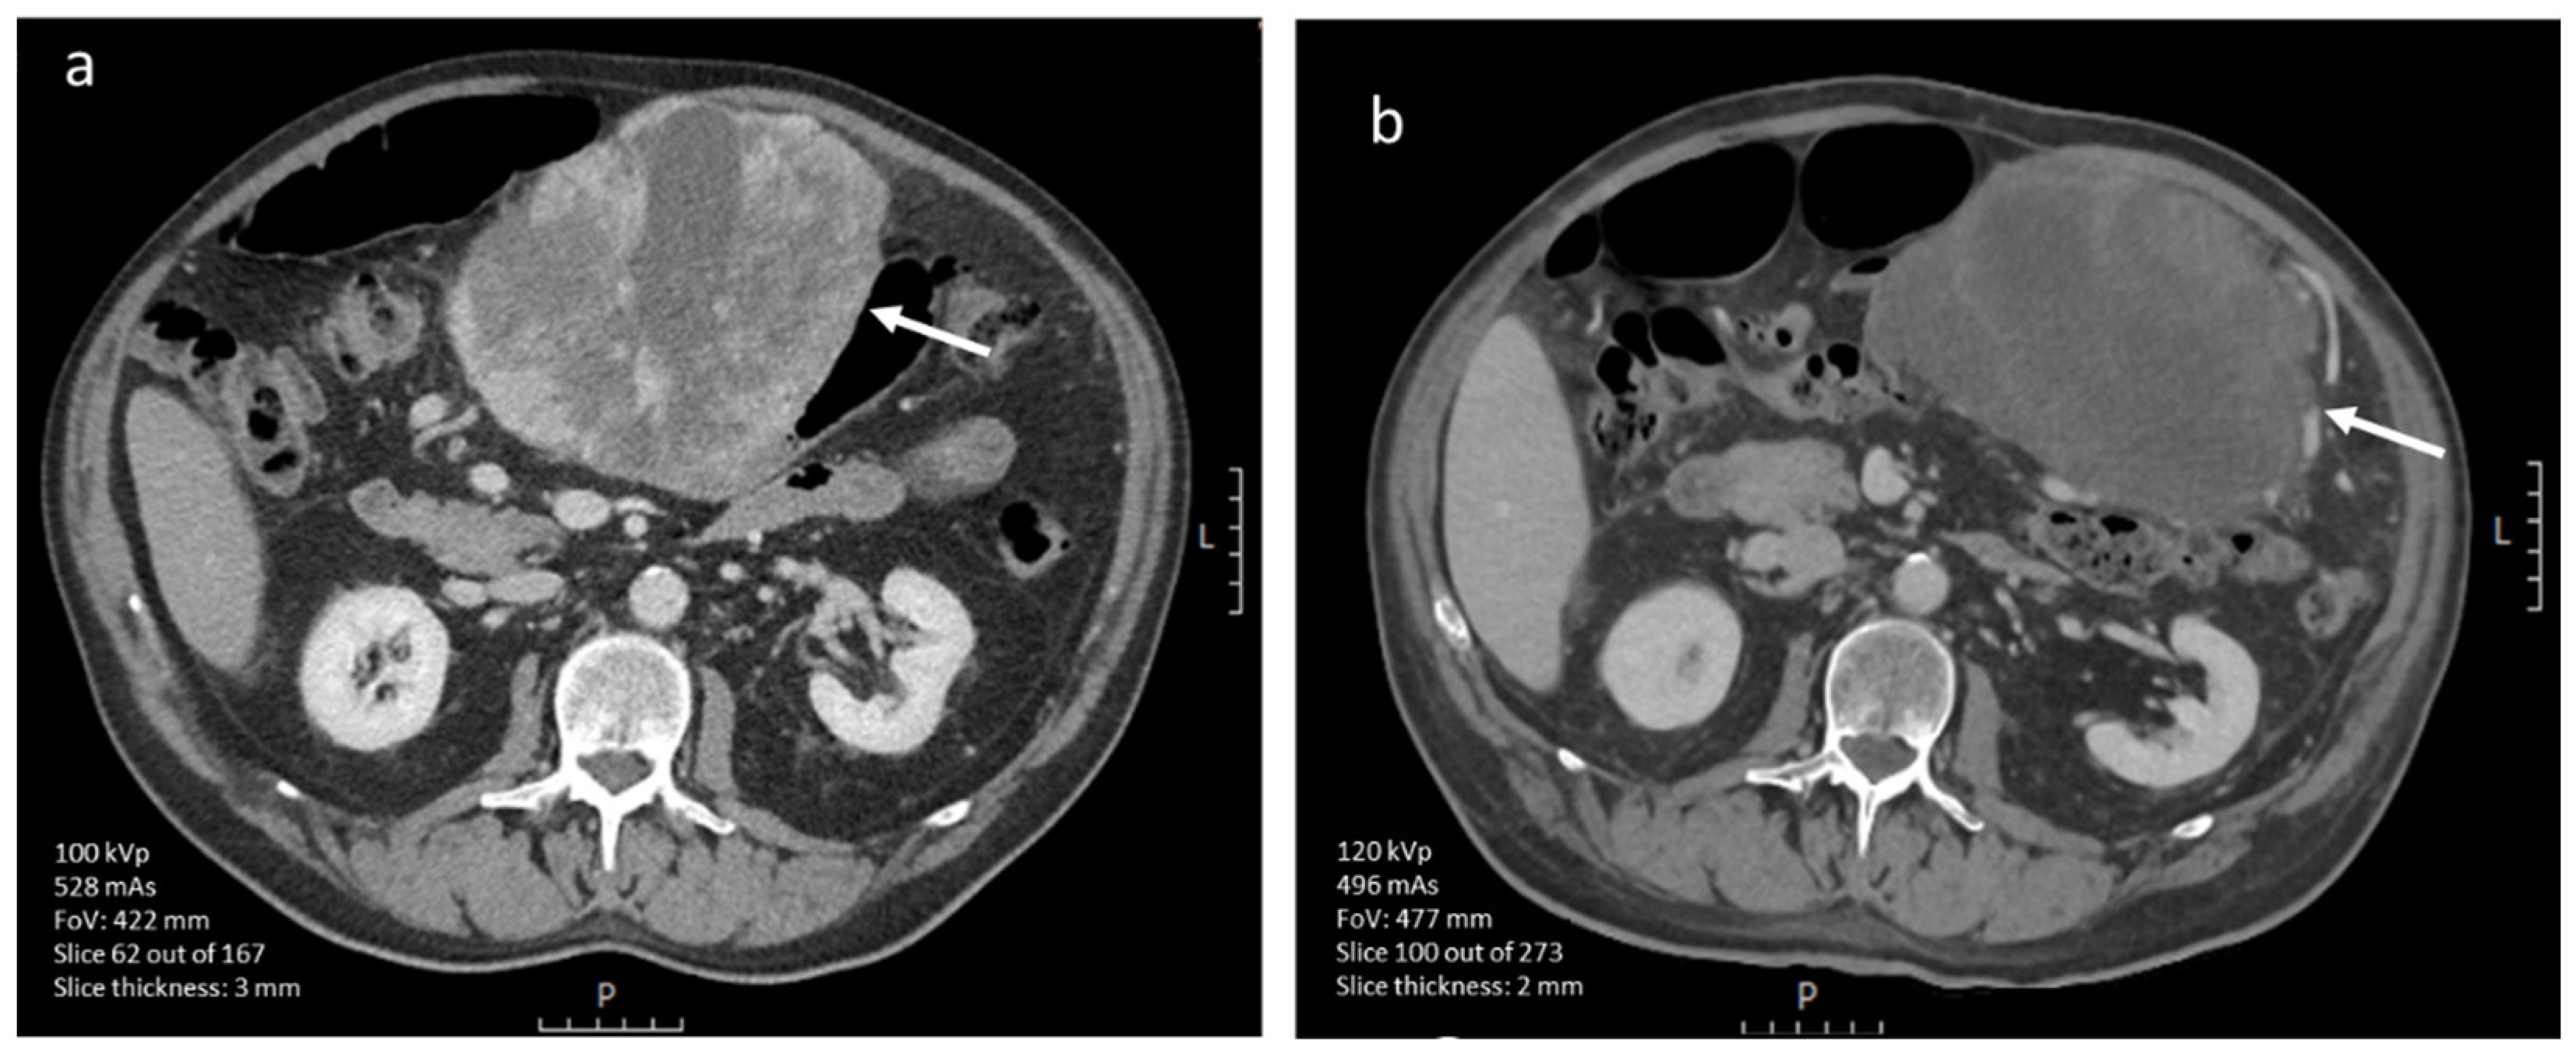

3.4.1. CE-CT Imaging